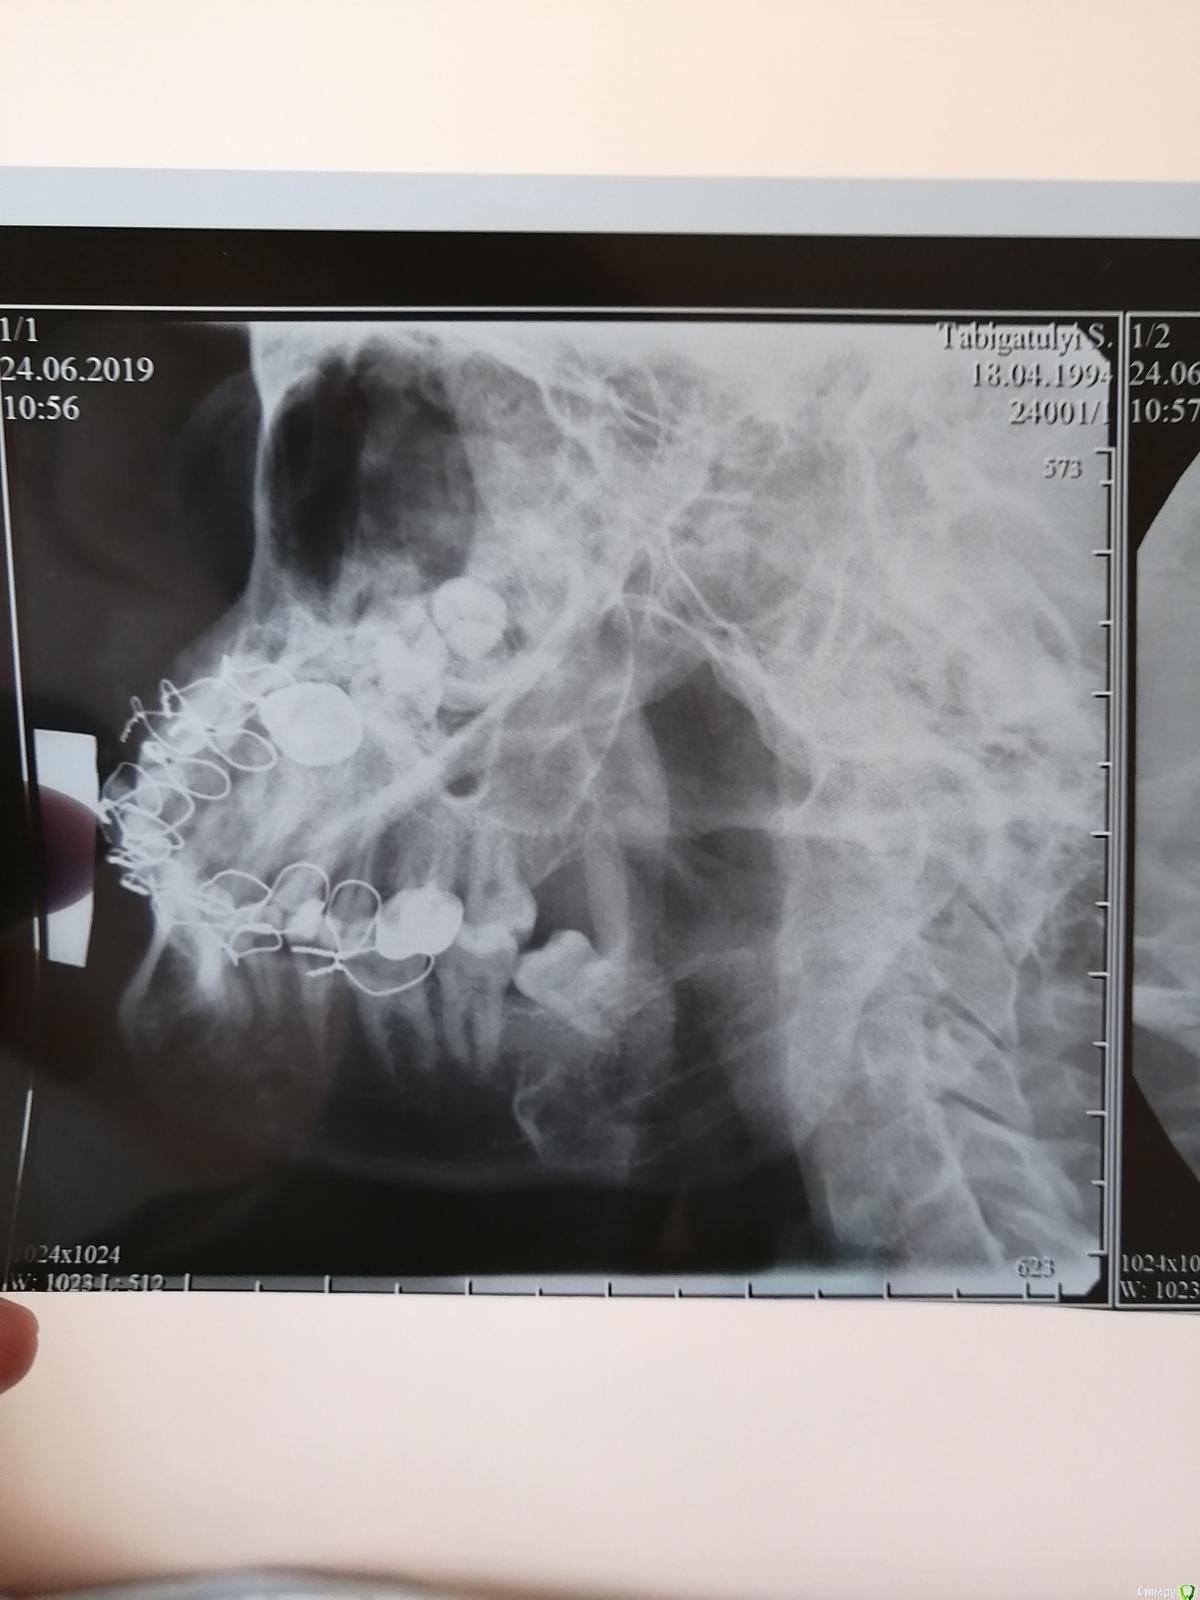

Blazingstar Опубликовано 16 июля, 2019 Поделиться Опубликовано 16 июля, 2019 (изменено) Перелом венечного отростка со смещением отломков. Сломал челюсть 16 июня прошлого месяца, обратился с болями в местную больницу к стоматологу, прописали антибиотики и сказали, что всё срастётся главное нё кушай твёрдое, потом 21 июня по собственной инициативе обратился в Члх, там сразу поставили шины если её не ставить сказали потом рот будет вонять всегда, там лежал 10 дней, в стационаре кололи антибиотики и вот сняли сегодня шины в местной больнице стоматолог посоветовал не есть три четыре дня твёрдую пищу. Во время лечения резинки не меняли ни разу когда лежал в стационаре и после в местной больнице, советовали только ромашкой полоскать. Пожалуйста посмотрите снимок срастётся ли всё нормально операцию не делали. Завтра на работу еду на вахту 15 дней. После снимок не делали. В стационаре сделали снимок зубов только спустя три дня, место перелома не снимали. Где череп это снимок до шинирования, остальные снимки после шинирования спустя три дня сделано(там не видно место перелома) . Изменено 16 июля, 2019 пользователем Blazingstar Ссылка на комментарий